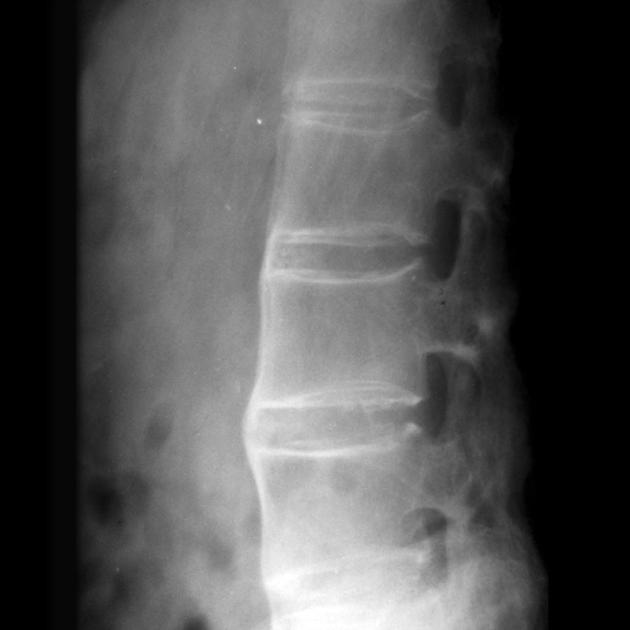

作为一种主要侵犯脊柱和骶髂关节的慢性炎症性疾病,强直性脊柱炎在我国的患病率约为0.3%,这意味着每1000个人中就有3个人可能受到它的困扰

别被这个拗口的医学名词吓到,其实强直性脊柱炎就像是脊柱的"生锈"过程,关节逐渐变得僵硬,活动受限